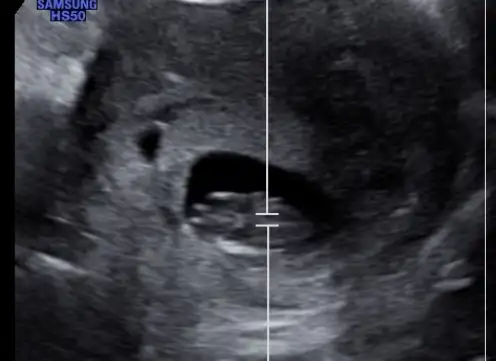

Bebek ve plesenta sol yerleşimli ultrasonda. İlk teori olarak erkekKese de armuta benzer olunca erkek diyolar, benim arkadasın kesesi sizinki gibiydi erkek onunki. İnsan 2 duyguyuda tatmak istiyor anlıyorum, inşAllah bir oğlan nasip olur size. Benim ilk çocuk, farketmez cinsiyeti

Plesenta çok ortada, kız olabilir gibi geldi bana